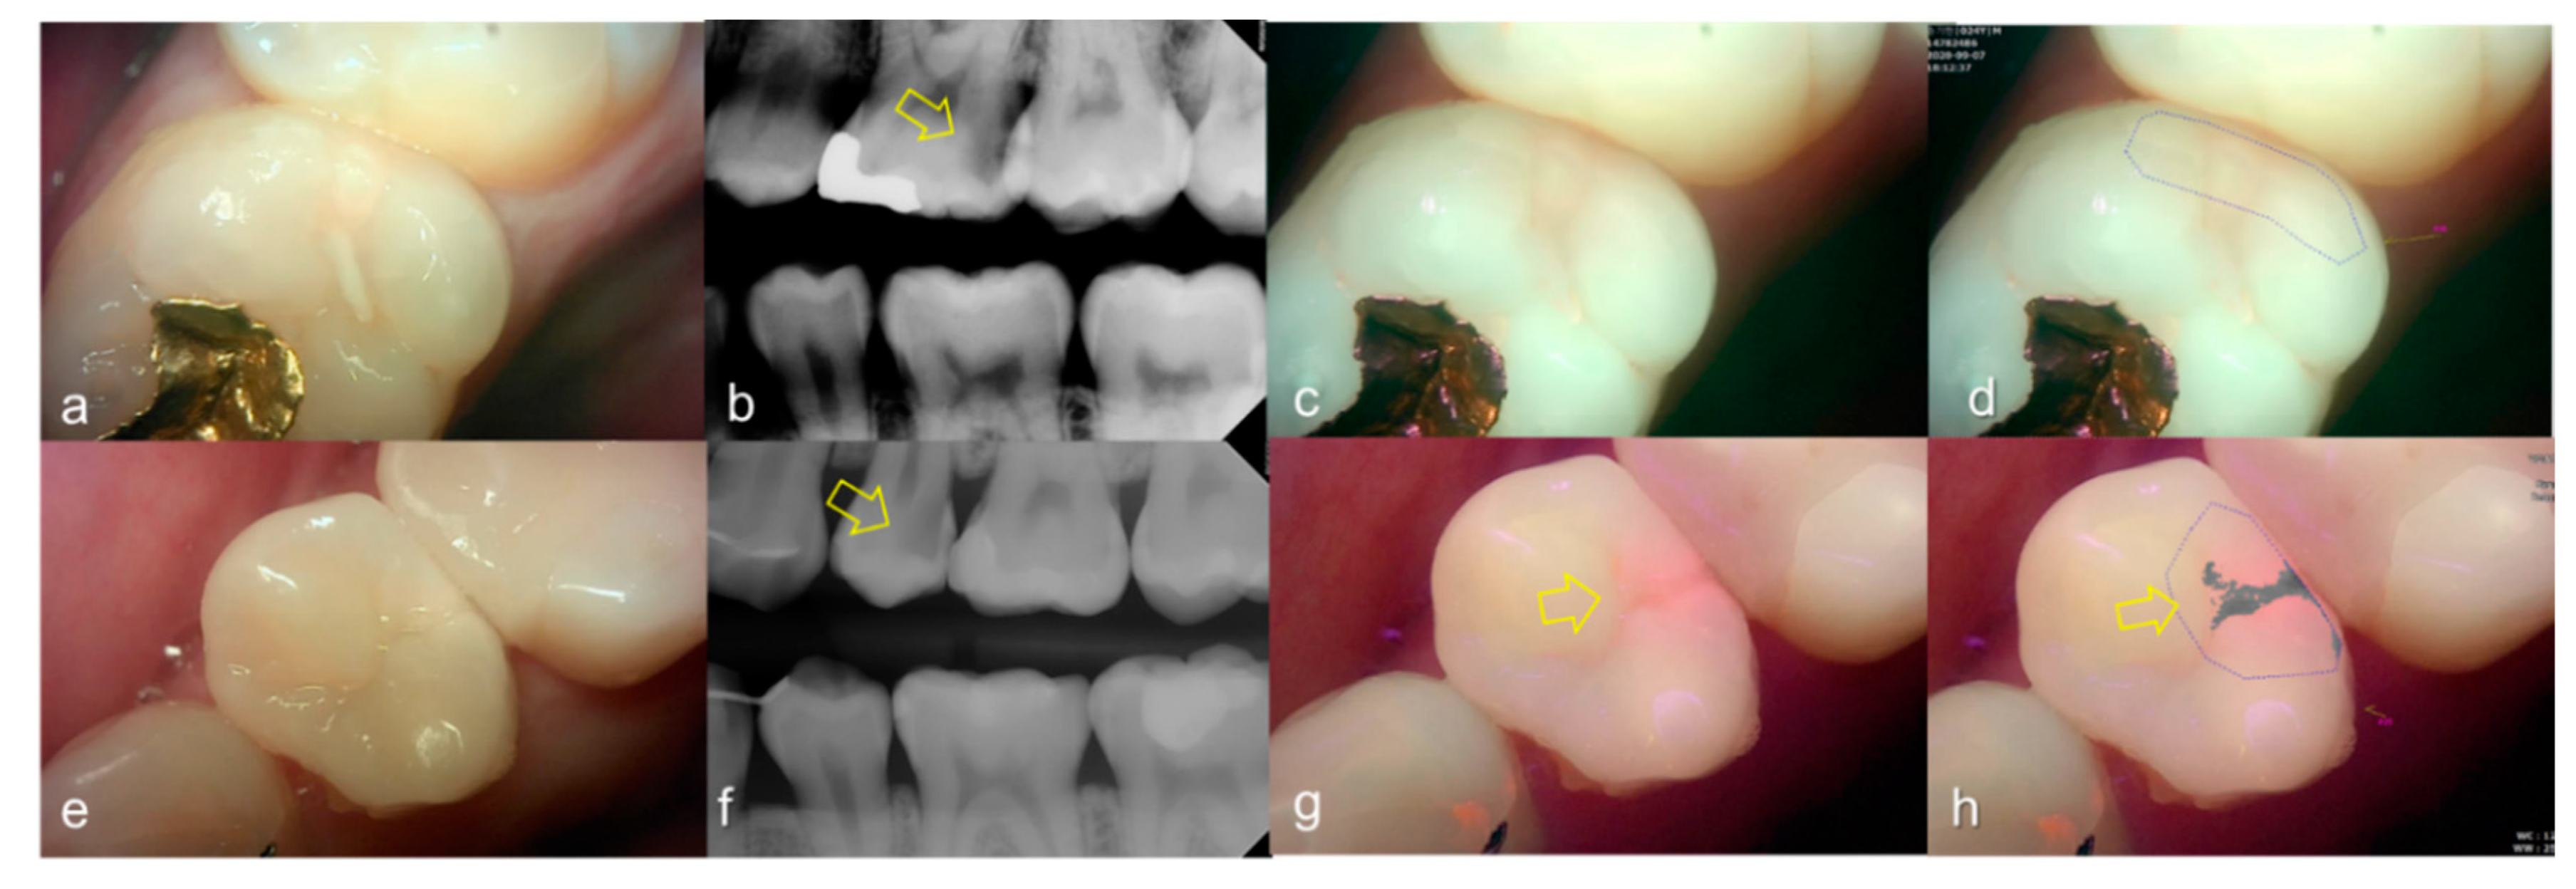

Figure 5.

Occlusal dental caries: (a–d) QLF caries score 2 (fluorescence loss and red fluorescence glow extending around pits and fissures) and radiographic caries score 3 (radiolucency extending to the middle 1/3 of the dentine) on #47; (e–h) QLF caries score 3 (red fluorescence glow extending around pits and fissures and a dark shadow from dentin present) and radiographic caries score 3 (radiolucency extending to the middle 1/3 of the dentine) on #37; (i–l) QLF caries score 3 (red fluorescence glow extending around pits and fissures and a dark shadow from dentin present) and radiographic caries score 3 (radiolucency extending to the middle 1/3 of the dentine) on #47; (a,e,i): white-light image of QLF; (b,f,j): fluorescence image of QLF; (c,g,k): bitewing radiograph; (d,h,l): analyzed QLF image using QA2 software.